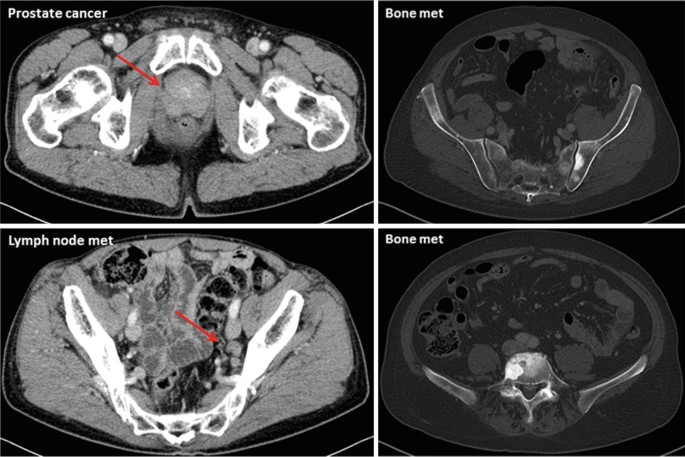

This paper was presented at the 2023 American Society of Clinical Oncology (ASCO) held in Chicago Illinois by Drs Catherine Handy Marshall, Benjamin A. Teply,